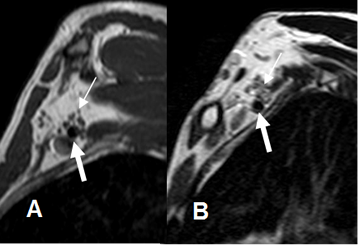

Fig 6. Mielografía normal.

A: Mielografía por RM lateral y B: Mielografía por RM AP. Estudio normal, donde se aprecia la salida de las raíces.